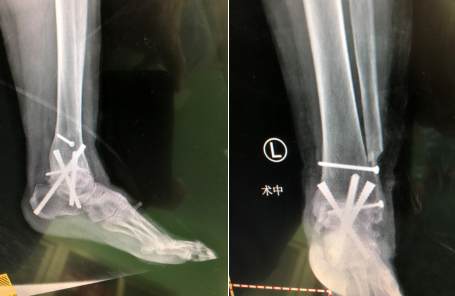

“患者是位老年女性,20年前脚踝有过扭伤,后期疼痛不断加重,近来不能长时间走路。到咱们医院一检查,双侧踝关节炎,左侧的距下关节也出现病变,患者想改善症状,我们把病人的检查结果发给俞教授看,一起进行评估,选择了一种最适合患者的治疗,因为目前左侧比较重,就把左侧踝关节距下关节都做了融合,把后足的跟骨、距骨、胫骨钉死,把脚踝放正,以后她的走路就会好很多。”参与手术的赵亮医生说。

王大妈的病情比较严重,也比较典型,曹主任将患者资料发给了上海同济医院的俞光荣教授,远程进行了病情讨论。很快,俞教授决定在9月5日来sararz坐诊时和曹广超主任手术团队一起为王大妈实施手术。